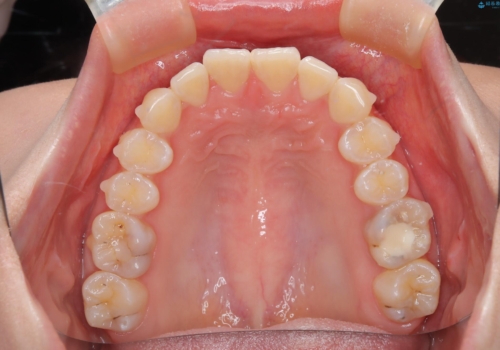

前歯のガタつきを治したい 翼状捻転マウスピース矯正

- 上顎前歯の突出、がたつき(翼状捻転)を主訴に来院されました。当院では総合歯科医療が可能であるため、矯正前処置として虫歯治療・歯周治療、親知らず抜歯を施行しました。その後、非抜歯かつ口元が出ないようなマウスピース治療を行いました。仕事柄、1日の装着時間が短くなってしまう時期もありましたが、患者様と相談しながら問題なく終了しています。